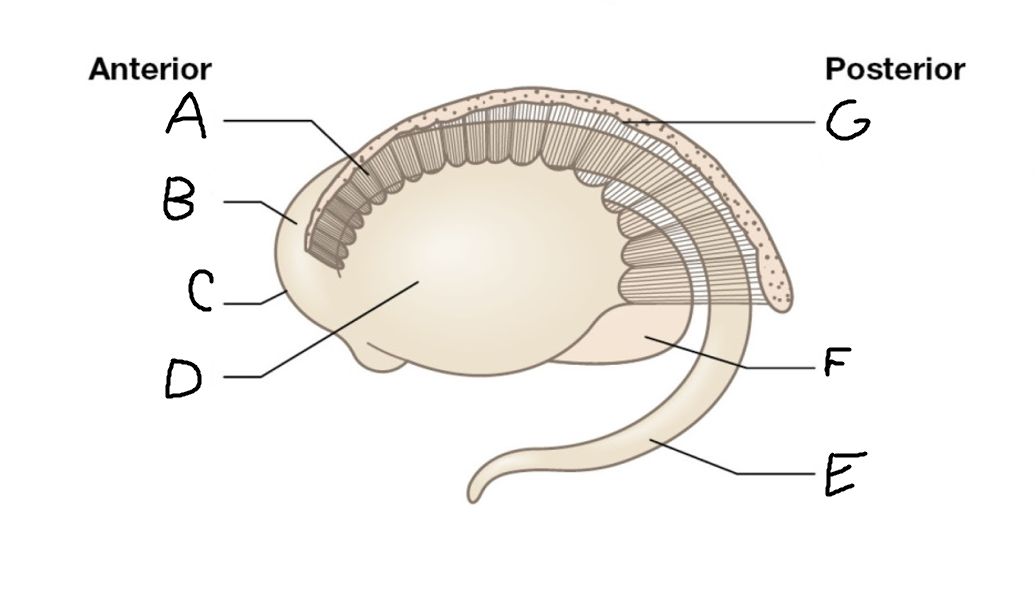

caudate nucleus head

A

Putamen

B

caudate nucleus tail

C

Lateral ventricle

D

caudate nucleus body

E

internal capsule

F